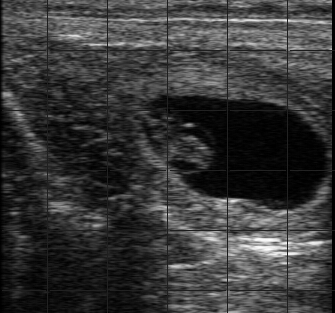

兽用B超图像的形成是靠波束传输形成的。兽用B超图像采取多段聚焦的时候,为获得一条扫描线的兽用B超图像,超声在动物体需要来回传播几次。不难计算,当采用4端聚焦,采样深度为20cm,设声速为1540 m/s时,以256条线为一帧图像,系统的帧频会不足6帧。兽用B超图像增大发射焦距或减小发射孔径可以实现发射波束的弱聚焦。多波束合成可以提高兽用B超成像的帧频,兽用B超图像回波信号进过数字波束合成之后,就进入动态滤波这个环节,动态滤波是为了解决动物体组织对不同频率超声能量的衰减不同而提出的。动态滤波技术实现的好坏,直接关系到数字化兽用B超图像系统的成像分辨率,是成像系统的另一个关键组成部分。频率随深度衰减变化的归一化曲线示意图。 回波频率成分主要集中在高频,随着探测深度的增加,回波频率成分主要集中在低频。所以说波束的形成好坏直接影响到兽用B超图像的质量问题。